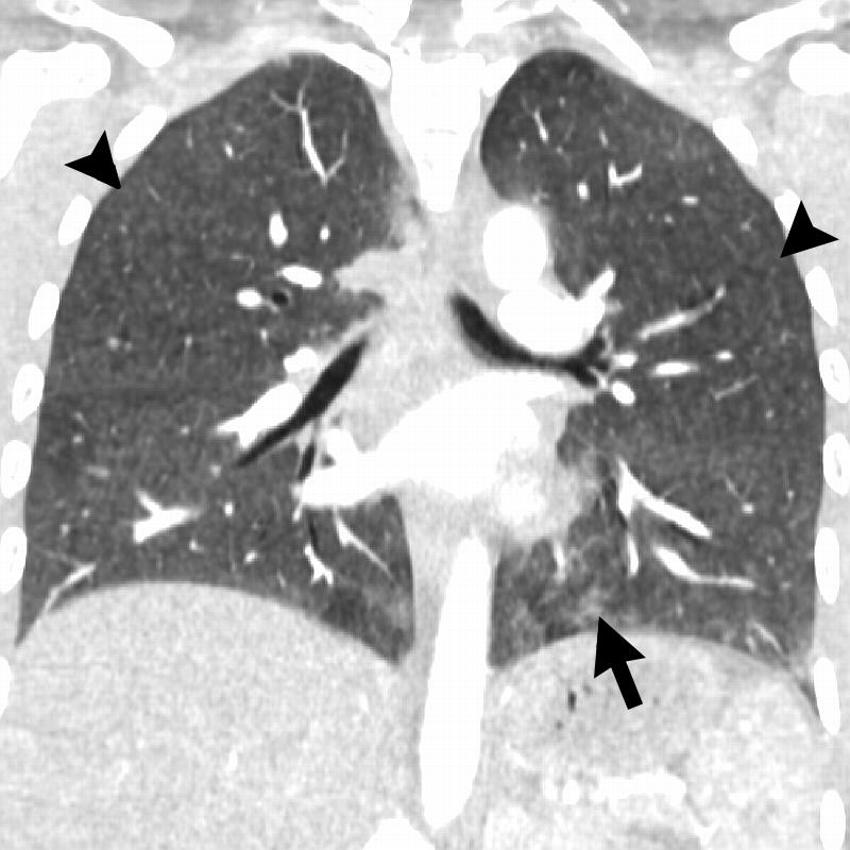

Figure 13. Coronal image shows hypersensitivity pneumonitis (HP) pattern in a 35-year-old man who vaped tetrahydrocannabinol products. Extensive hazy centrilobular nodularity (arrowheads) is most pronounced in midlung and upper lung zones consistent with inhalational injury. Mild ground-glass opacity is present as bases (arrow). This imaging pattern is commonly seen in HP. Patient’s condition rapidly improved after steroid administration and no biopsy was obtained. Although authors have seen a few cases with HP pattern, there are no cases in literature with pathologic confirmation. Other possible etiologies for diffuse pattern of centrilobular nodules in electronic cigarette or vaping product use–associated lung injury includes airway-centered foci of organizing pneumonia.

High-res (TIF) version